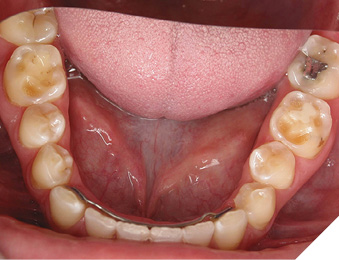

A 65-year-old woman comes to the office with the chief complaint of worn-down teeth, missing teeth, tooth sensitivity, especially on maxillary teeth and TMJ pain. Her past medical history was reviewed and was significant for asthma, insomnia, hypercholesterolemia, hypothyroidism, and anxiety disorder. She denied any sleep disturbances. Her medications included salbutamol, ezetimibe, quetiapine, and levothyroxine. She referred to being allergic to dust and shellfish and sensitive to propofol. She had a right mastectomy in 2014 due to breast cancer. No chemotherapy or radiation was done. Her diet was considered normal, and she denied any consumption of acidic drinks and denied any history of regurgitation. She denied any parafunctional habits during the day. She was using a maxillary transitional partial denture since she had lost some of her teeth due to fracture and caries. No other problems were evidenced. Intraoral exam showed moderate attrition lesions of posterior teeth, porcelain fused to metal crowns on teeth 46 and 47 had the porcelain portion worn down, exposing the metal substructure. Missing teeth included teeth 14,15,16,18,24,28, 36,38,48. Palatal surfaces of maxillary anterior teeth also appeared worn down. An abfraction lesion was found on tooth 23. No carious lesions were found in any of her teeth. Composite restorations on mandibular anterior teeth were chipped or were missing (Figs. 6-11) She also presented with limited mouth opening: 35 mm interincisal distance at maximum opening. There was bilateral pain on palpation of preauricular areas. Her pain was the worst early in the morning which suggested night parafunction. No crepitus, or joint clicking were found.

Fig. 7